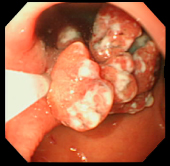

| 症例(胃ポリープ切除1) | |||

| ポリープ | 根元に生理食塩水を注入して水ぶくれ状態をつくり、膨らんだその部分に スネアをかけて高周波の電流を流し病変部を焼き切っている状態。 |